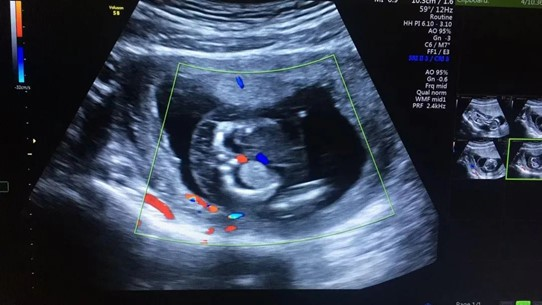

張女士本來是打算到武漢仁愛醫(yī)院做完產(chǎn)檢后,就和家人一起回老家過春節(jié),沒想到超聲檢查篩查出胎兒全身皮膚水腫,頸部淋巴水囊瘤,雙側(cè)胸腔積液,檢查醫(yī)生立刻叫來了武漢仁愛醫(yī)院超聲科主任王娟進(jìn)行再次檢查,確診了胎兒的異常情況。

張女士超聲檢查結(jié)果

“在這種情況下,胎兒需要進(jìn)行染色體的進(jìn)一步檢查,如果染色體有問題,就要盡早終止妊娠。”王娟介紹,造成這一現(xiàn)象最常見的原因是孩子的染色體異常,在得了淋巴水囊瘤的孩子中,有70%是存在染色體異常的,這個(gè)和年齡相關(guān),年齡越大發(fā)生的概率越高,而這些孩子在早期如果出現(xiàn)了水腫,90%以上都不能夠存活,所以建議盡早終止妊娠。